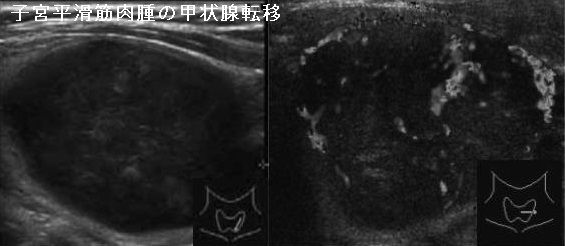

子宮平滑筋肉腫(uterine leiomyosarcoma:uterine sarcoma)の甲状腺転移は非常にまれです。子宮平滑筋肉腫は婦人科腫瘍の中でも特に予後不良で、早期より肺・肝臓・腎臓・脳・骨へ血行性転移します。子宮頸癌に対する根治的放射線治療など、骨盤への放射線照射との関連が強い。[Oncol Res Treat. 2018;41(11):680-686.][Int J Gynecol Pathol. 2017 Jan;36(1):31-41.]

子宮平滑筋肉腫の甲状腺転移は

- 50代女性に多い

- 全身への遠隔転移の一部分として発症

- 頸部腫大、あるいは全身の遠隔転移検索で見つかる

- 穿刺細胞診による正診率は100%、紡錘形細胞と異型細胞を認める

甲状腺未分化癌 と診断されたケースもある[Malays J Pathol. 2021 Apr;43(1):69-73.] - 気道閉塞や両側反回神経麻痺があれば甲状腺摘出手術

[Thyroid. 2007 Dec;17(12):1295-7.](Int J Gynecol Cancer 16 : 442-445, 2006)

さらに、子宮平滑筋肉腫の甲状腺転移は、甲状腺原発の平滑筋肉腫と鑑別が必要(稀中の稀、誰も知らない甲状腺平滑筋肉腫)(World J Clin Cases. 2019 Feb 26;7(4):473-481.)。

下は、子宮平滑筋肉腫の甲状腺転移 超音波(エコー)画像(内分泌甲状腺外会誌 32(3):205-210,2015)